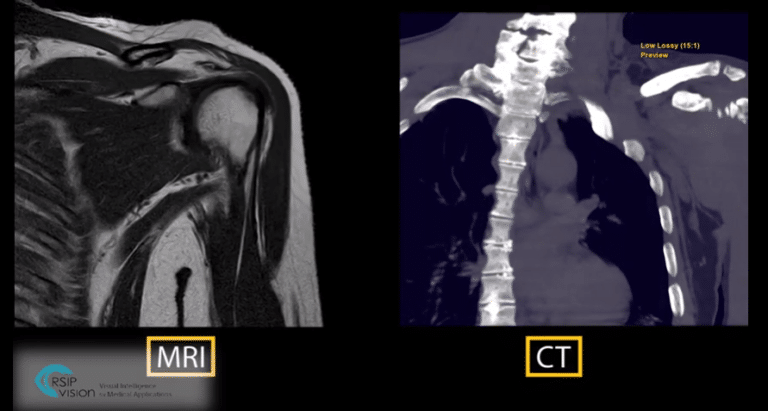

RSIP Vision Presents New Tool for Total Shoulder Arthroplasty (TSA) Planning Through MRI Scan Advanced artificial intelligence creates accurate and radiation-free method for TSA planning.